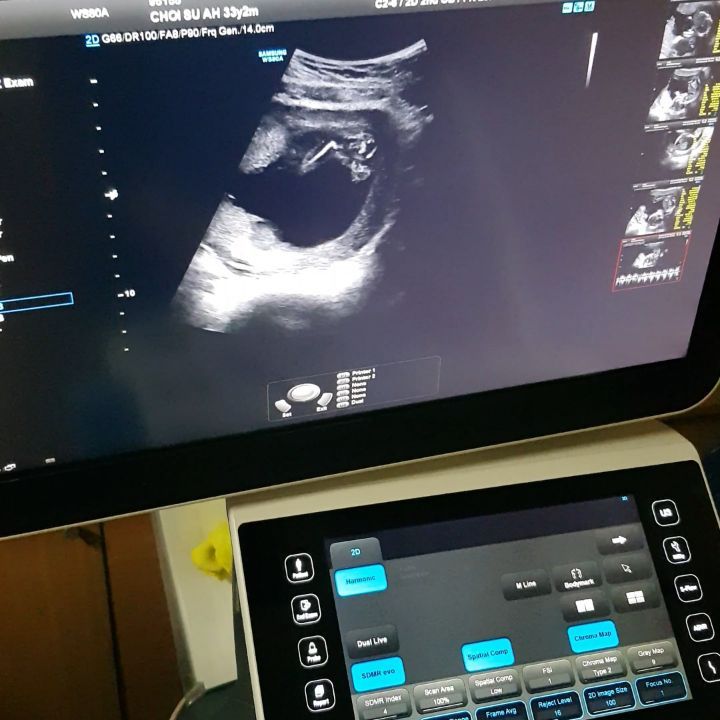

25일 정재형이 게시한 최근 게시물에는 “우리 깜찍이 16주차 ㅎㅎㅎ아직 성별을 알려주는건 불법이래서..여자앤지 남자앤지 모르겠지만...남자면”라는 글과 함께 사진이 담겨 시선을 끌었다.